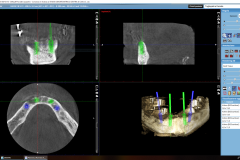

• Tac 3D (tecnologia Cone-Beam)